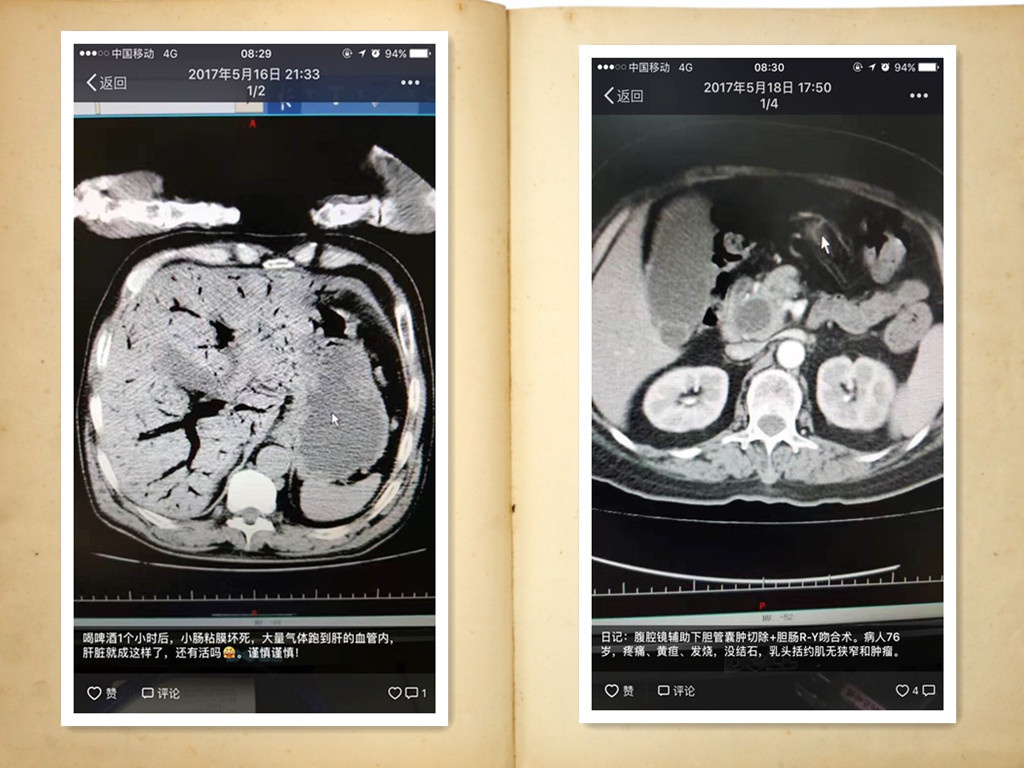

而我们廖主任的朋友圈则是长这样

善意提示:用餐者或晕血者请有思想准备后再进行观看!

考虑到大家的感受,我们没有贴大图, 再来几张缓和点的吧。

也许有些人会觉得太重口味,接受不了,但是小编想说,正是从廖主任的朋友圈,让我们看到了一个对自己严格要求,对待病症精益求精,对待患者认真负责的好医生。走进区医院普外科的病房,你就会看到,楼道间的通知栏上贴满了患者的感谢信,字里行间都是对廖主任,对普外科医护人员的深深感谢之情。

通过廖主任的朋友圈你也会发现,他擅长癌症等复杂疑难疾病的诊治,有来自全国各地的肿瘤疑难疾病患者慕名求治。